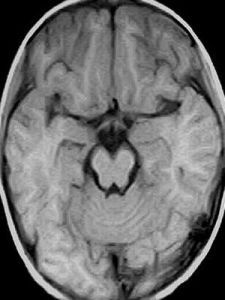

1磁共振最常用的核是氫原子核質子(1H),因為它的信號最強,在人體組織內也廣泛存在。影響磁共振影像因素包括:(a)質子的密度;(b)弛豫時間長短;(c)血液和腦脊液的流動;(d)順磁性物質(e)蛋白質。磁共振影像灰階特點是,磁共振信號愈強,則亮度愈大,磁共振的信號弱,則亮度也小,從白色、灰色到黑色。各種組織磁共振影像灰階特點如下;脂肪組織,松質骨呈白色;腦脊髓、骨髓呈白灰色;內臟、肌肉呈灰白色;液體,正常速度流血液呈黑色;骨皮質、氣體、含氣肺呈黑色。

磁共振影像灰階特點是,磁共振信號愈強,則亮度愈大,磁共振的信號弱,則亮度也小,從白色、灰色到黑色。

各種組織磁共振影像灰階特點如下:脂肪組織,松質骨呈白色;腦脊髓、骨髓呈白灰色;內臟、肌肉呈灰白色;液體,正常速度流血液呈黑色;骨皮質、氣體、含氣肺呈黑色。

1、顱腦與脊髓MRI對腦腫瘤、腦炎性病變、腦白質病變、腦梗塞、腦先天性異常等的診斷比CT更為敏感,可發現早期病變,定位也更加準確。對顱底及腦幹的病變因無偽影可顯示得更清楚。MRI可不用造影劑顯示腦血管,發現有無動脈瘤和動靜脈畸形。MRI還可直接顯示一些顱神經,可發現發生在這些神經上的早期病變。MRI可直接顯示脊髓的全貌,因而對脊髓腫瘤或椎管內腫瘤、脊髓白質病變、脊髓空洞、脊髓損傷等有重要的診斷價值。對椎間盤病變,MRI可顯示其變性、突出或膨出。顯示椎管狹窄也較好。對於頸、胸椎,CT常顯示不滿意,而MRI顯示清楚。另外,MRI對顯示椎體轉移性腫瘤也十分敏感。